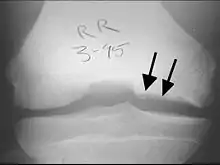

Tunnel or notch view X-ray of the right knee from a patient with osteochondritis dissecans—cystic changes and irregular border are indicated by arrows on the medial side compared to the lateral side

X-rays show lucency of the ossification on the anterior aspect of the knee in juvenile patients. In older people, the lesion typically appears as an area of osteosclerotic bone with a radiolucent line between the osteochondral defect and the epiphysis. The visibility of the lesion depends on its location and on the amount of knee flexion used. Harding described the lateral X-ray as a method to identify the site of an OCD lesion.[36]